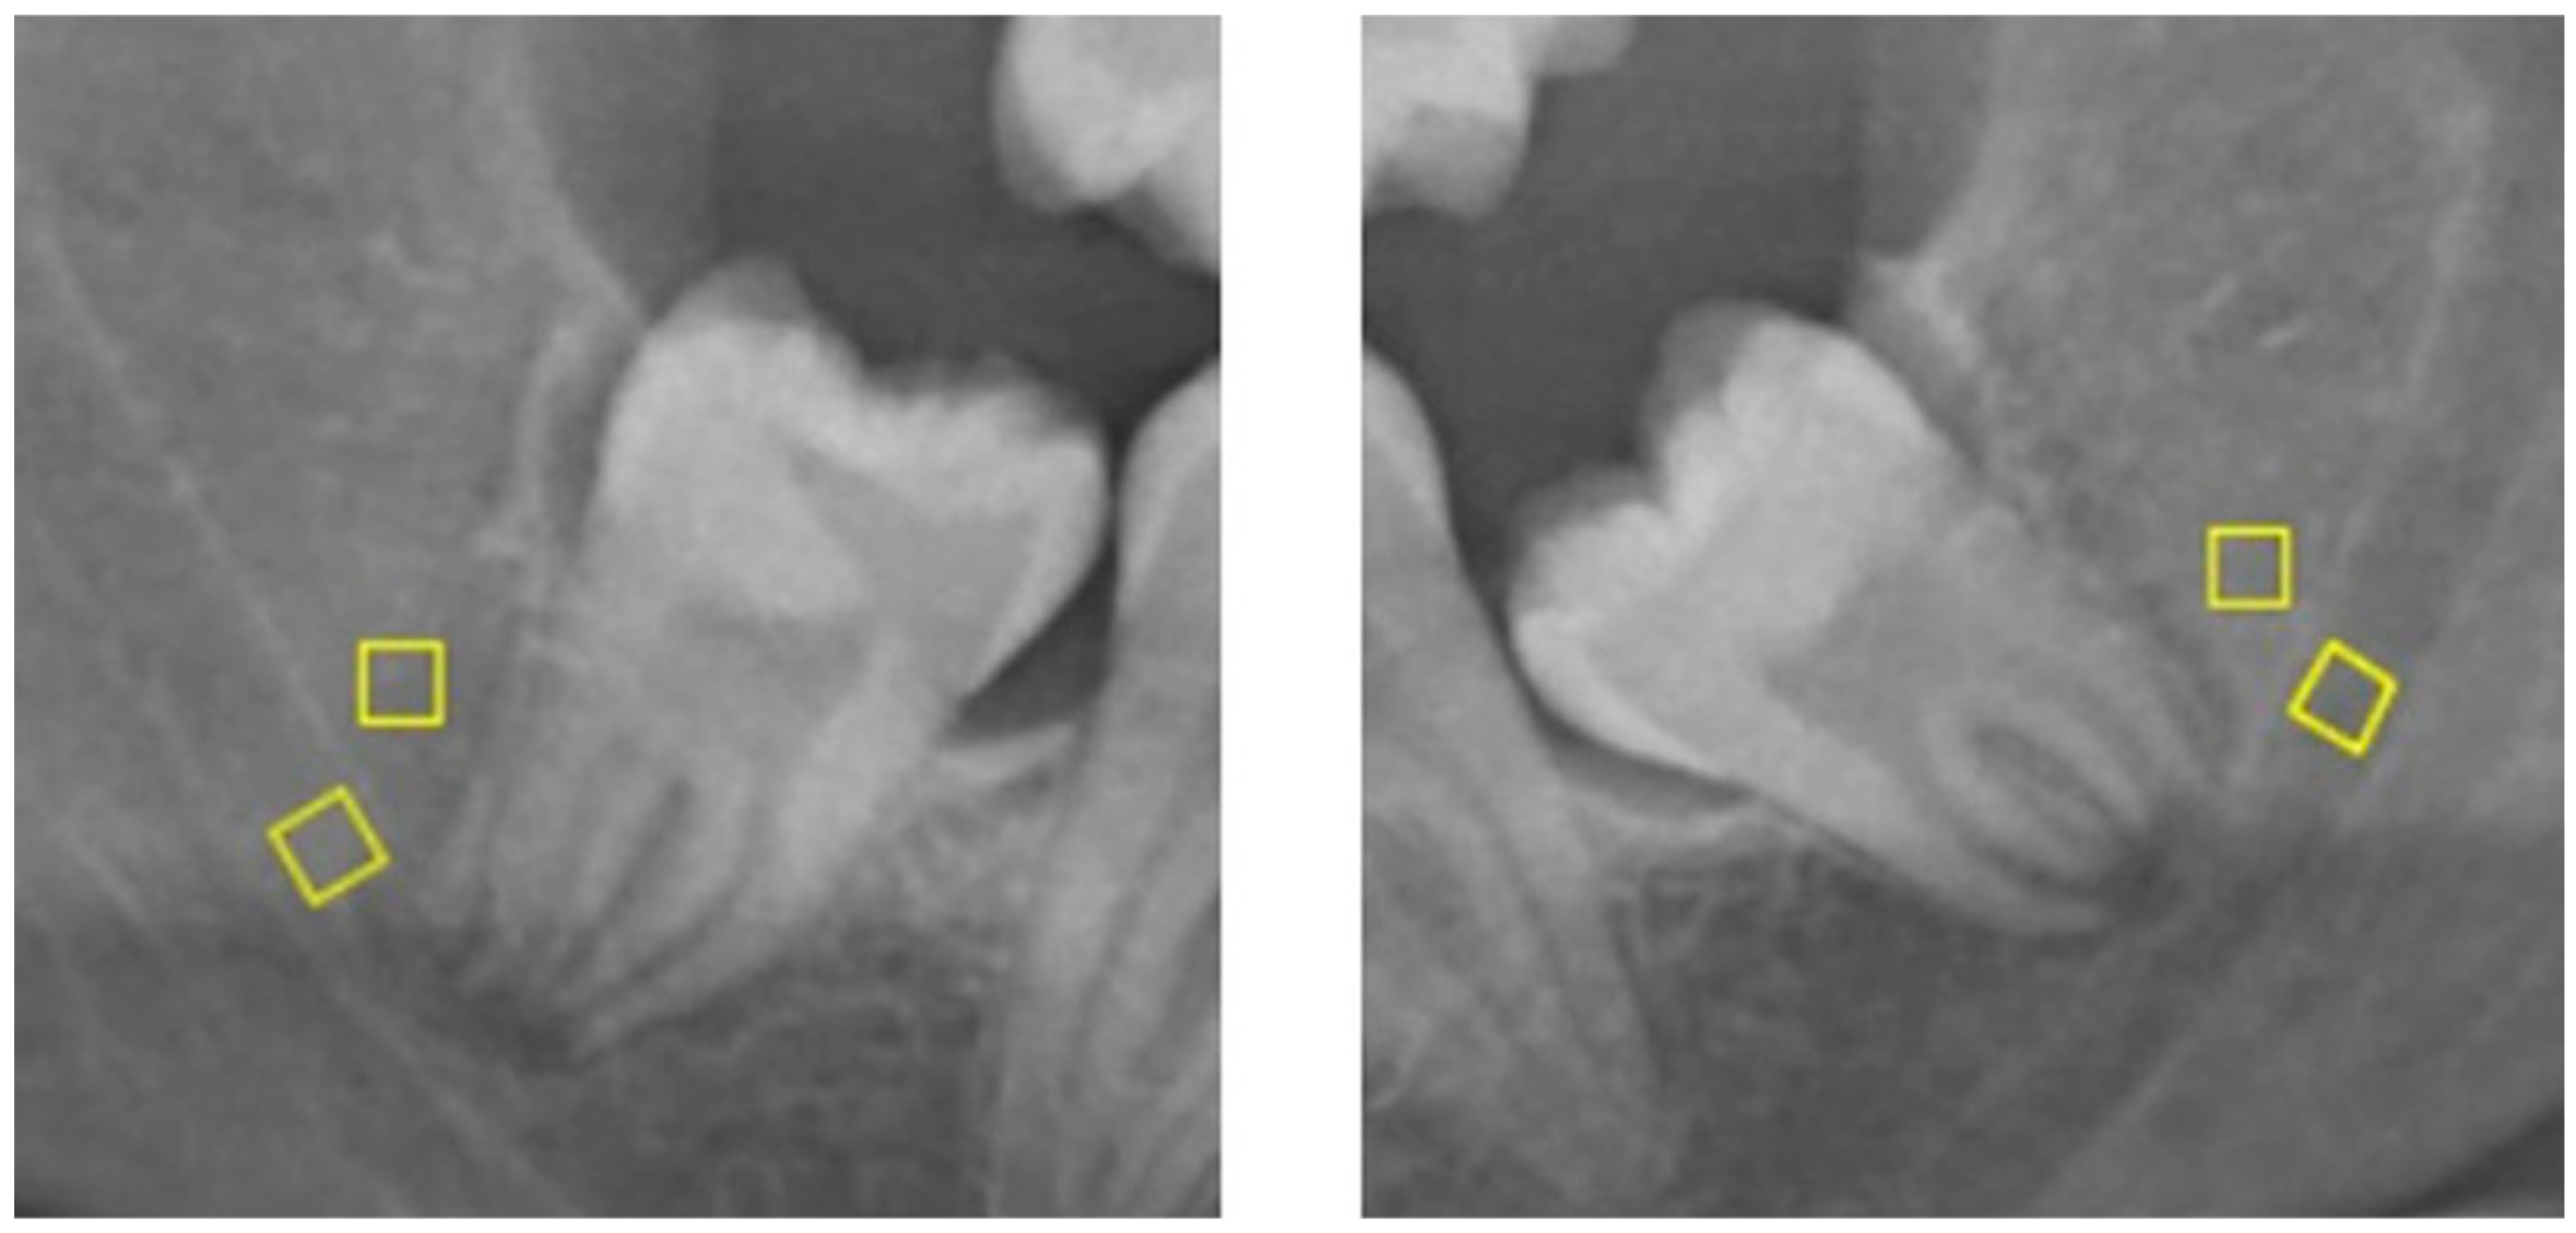

- a)

- Radiolucency at the root

- b)

- Narrowing of the root

- c)

- Radiolucency and bifurcation at the root apex

- d)

- Discontinuity of the mandibular canal cortex

- e)

- Narrowing of the mandibular canal

- f)

- Deviation of the root

- g)

- Deviation of the mandibular canal

- h)

- Superimposition of the root and the mandibular canal (overlapping)